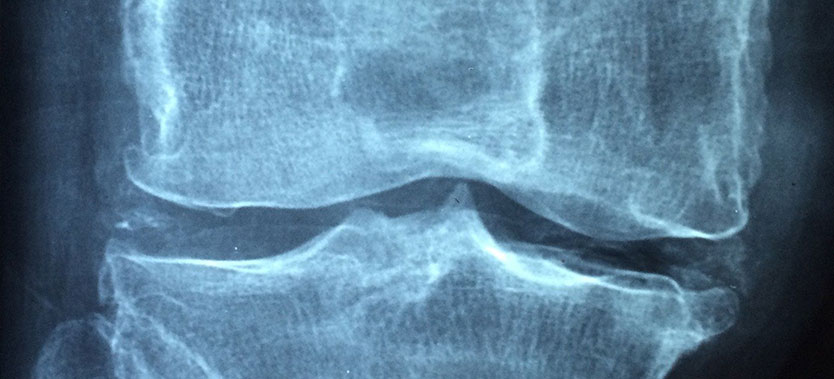

- Testare imagistica – Raze X, Tomografie computerizata CT, Imagistica prin rezonanta magnetica RMN, Ultrasunete.